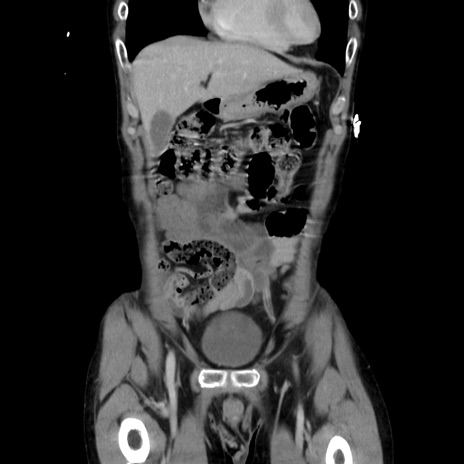

症例37(冠状断像)

【症例】40歳代 男性

【主訴】腹痛

【現病歴】4時間ほど前に電車に乗車中に臍部上より腹痛出現。徐々に増悪し起立困難となり、救急外来受診。生ものは数日食べていない。今朝お雑煮を食べた。

【身体所見】BT 36.8℃、BP 117/84mmHg、HR 91/min、SpO2 97%、苦悶様、腹部:臍上部広範囲圧痛あり、反跳痛±

【データ】WBC 8100、CRP 0.03